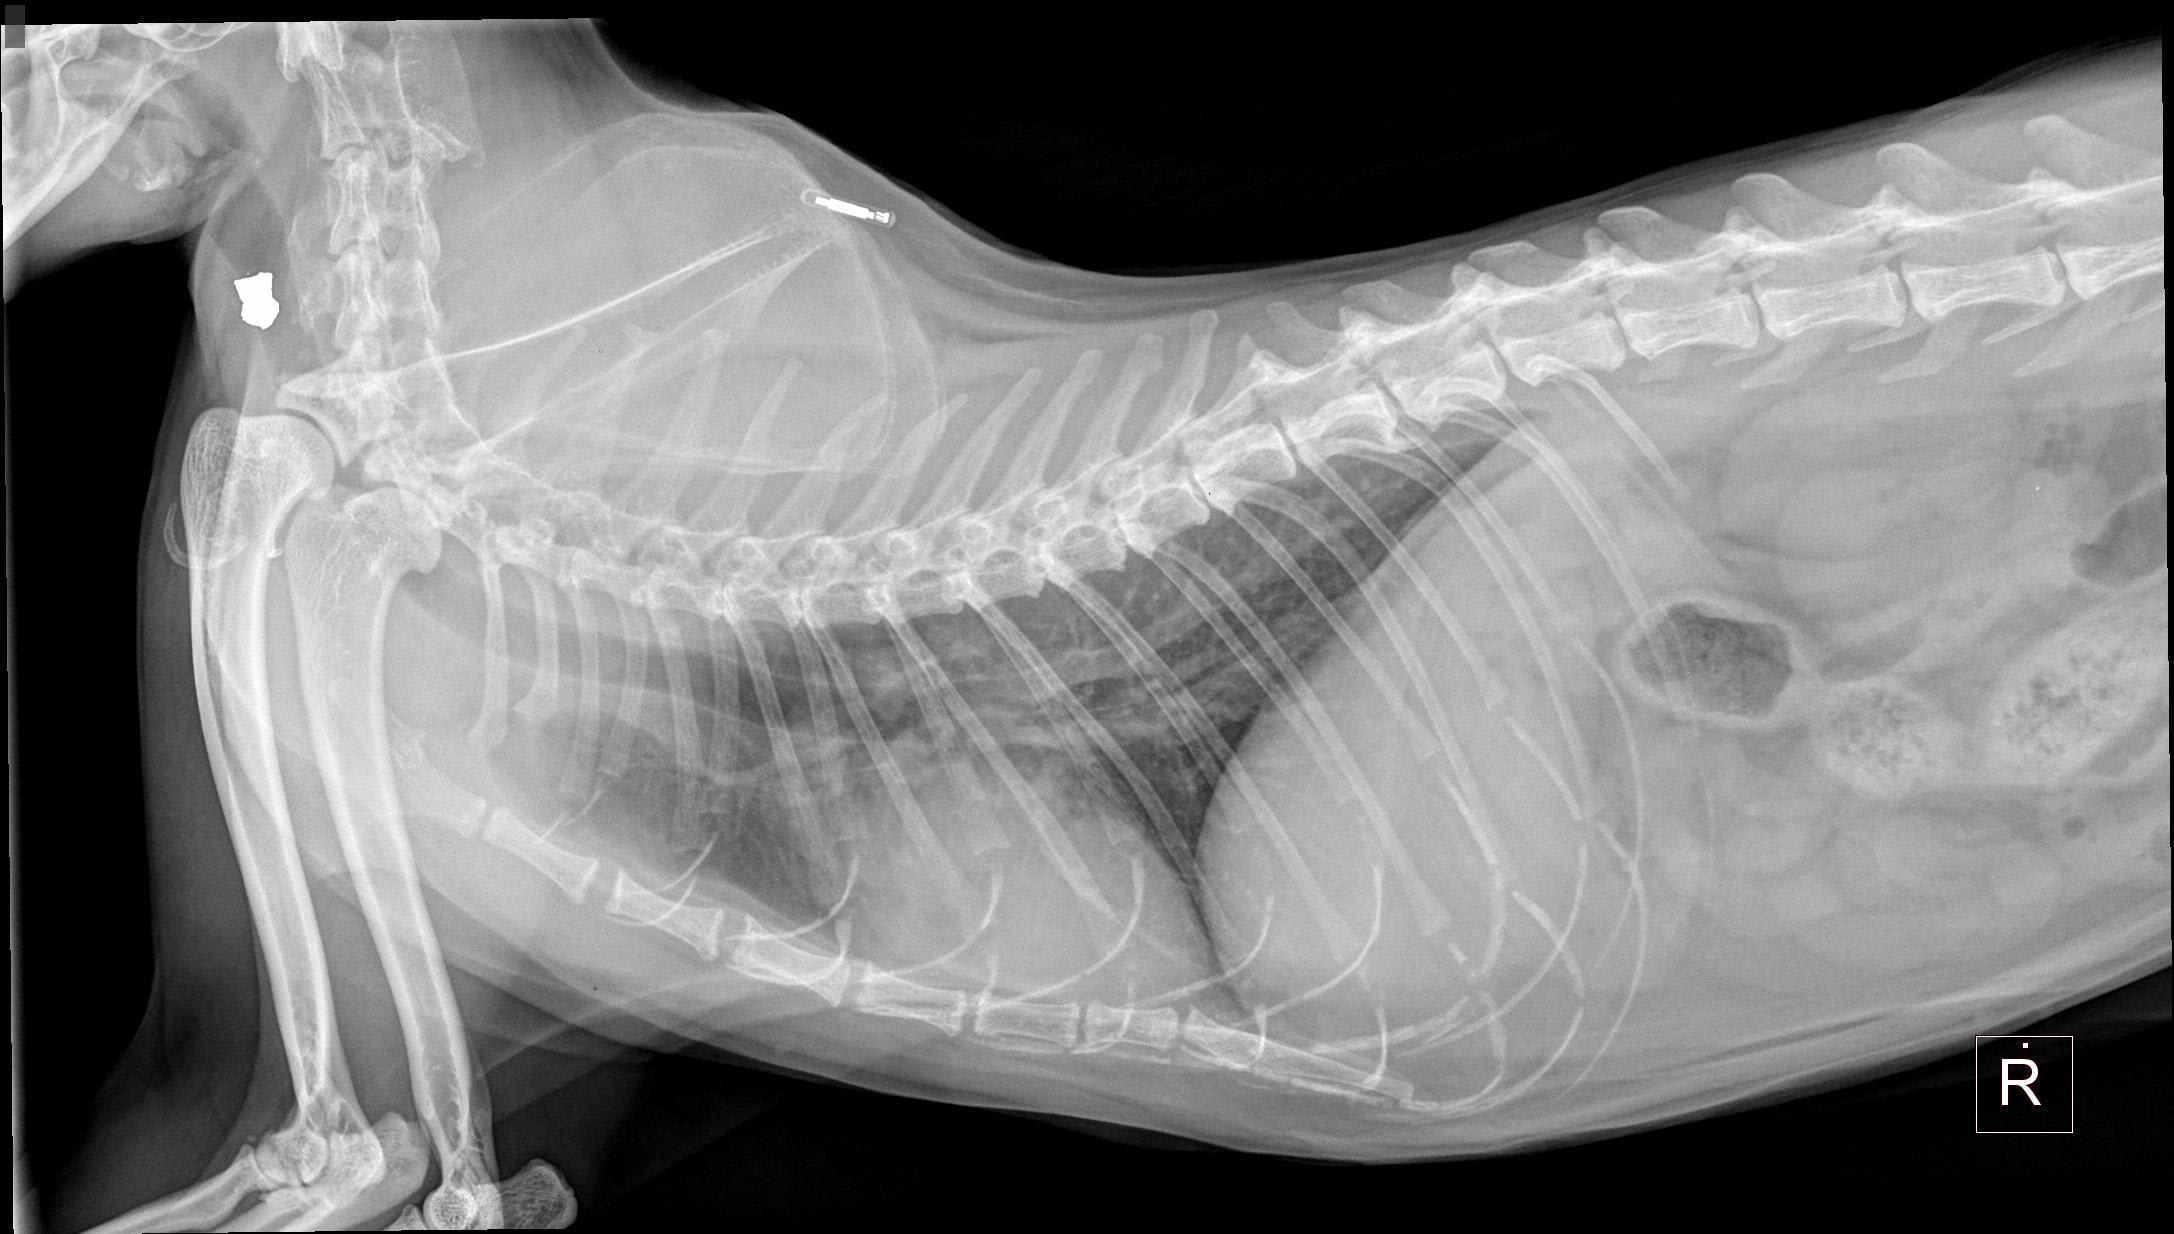

Hi there ! I was looking at my kitty's xray they took a couple of months ago before her dental and noticed those two white things . Is that part of the xray /supposed to be there ? Thank you !

Hi. Thanks for using Petco Pet Education Center, formerly Petcoach. The white spot along her back is a microchip. I’m unsure what the Pacitti along her throat is, it’s possible it may just be a marker used by the veterinarian, or maybe metal if she was wearing a collar or anything at the time of the radiograph. I recommend contacting your veterinarian for questions.